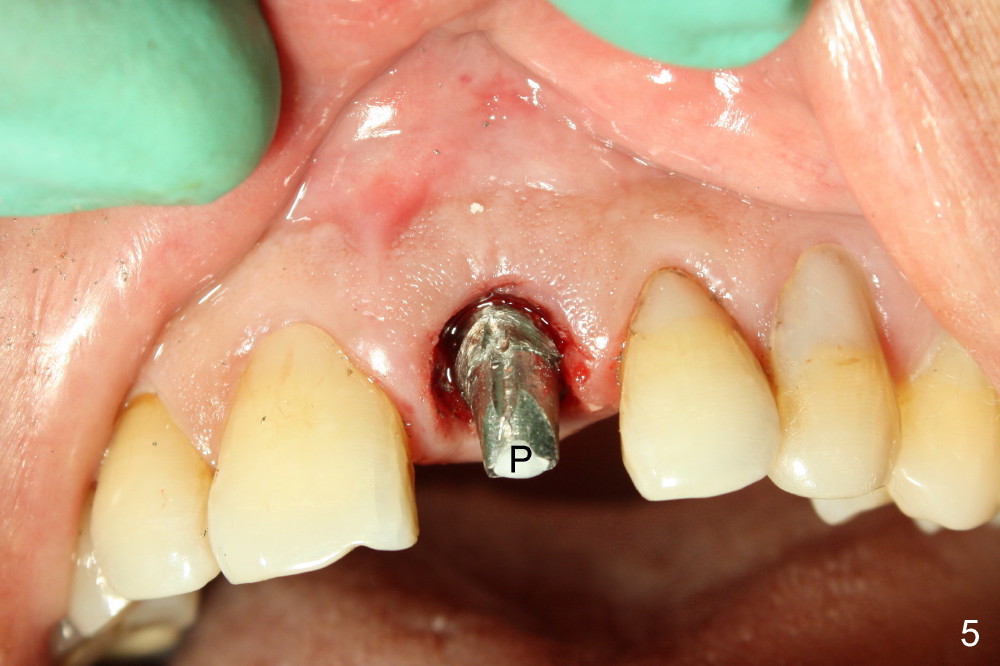

After extraction, osteotomy is made as palatally as possible so that the end of a reamer/drill (Fig.3 R) in the line of the incisal edge of the neighboring teeth. The depth of the 3.5 mm reamer is 14 mm from the crest (Fig.4 <). Next, a 5x17 mm tapered implant is placed with insertion torque > 60 Ncm (Fig.6). A 4 mm 0° unipost is permanently cemented (Fig.5: P). Finally a provisional is cemented on a temporary basis (Fig.7,8: T). There is no contact in centric or any lateral excursions.

Postop tenderness lasts for two days. The palatal swelling is unnoticeable 7 days postop (Fig.9 *, as compared to A in Fig.8). The bone remains stable around the implant (Fig.10), while the gingiva healthy around the immediate provisional (Fig.11) 5 months postop. Due to insurance limit, the permanent restoration is delayed (16 months postop, Fig.12). The patient is satisfied with the function and appearance 3 years 8 months postop (21 months post cementation, Fig.13,14). PA is taken 4 years 1 month postop (2.5 years post cementation, Fig.15). The lamina dura forms from the most coronal threads (Fig.16). Although there is no bone loss around the implant (Fig.17), metal starts to show 5 years 2 months postop (Fig.18 ^), probably related to the buccal placement, too large the implant for the site or buccal plate atrophy (Fig.19).